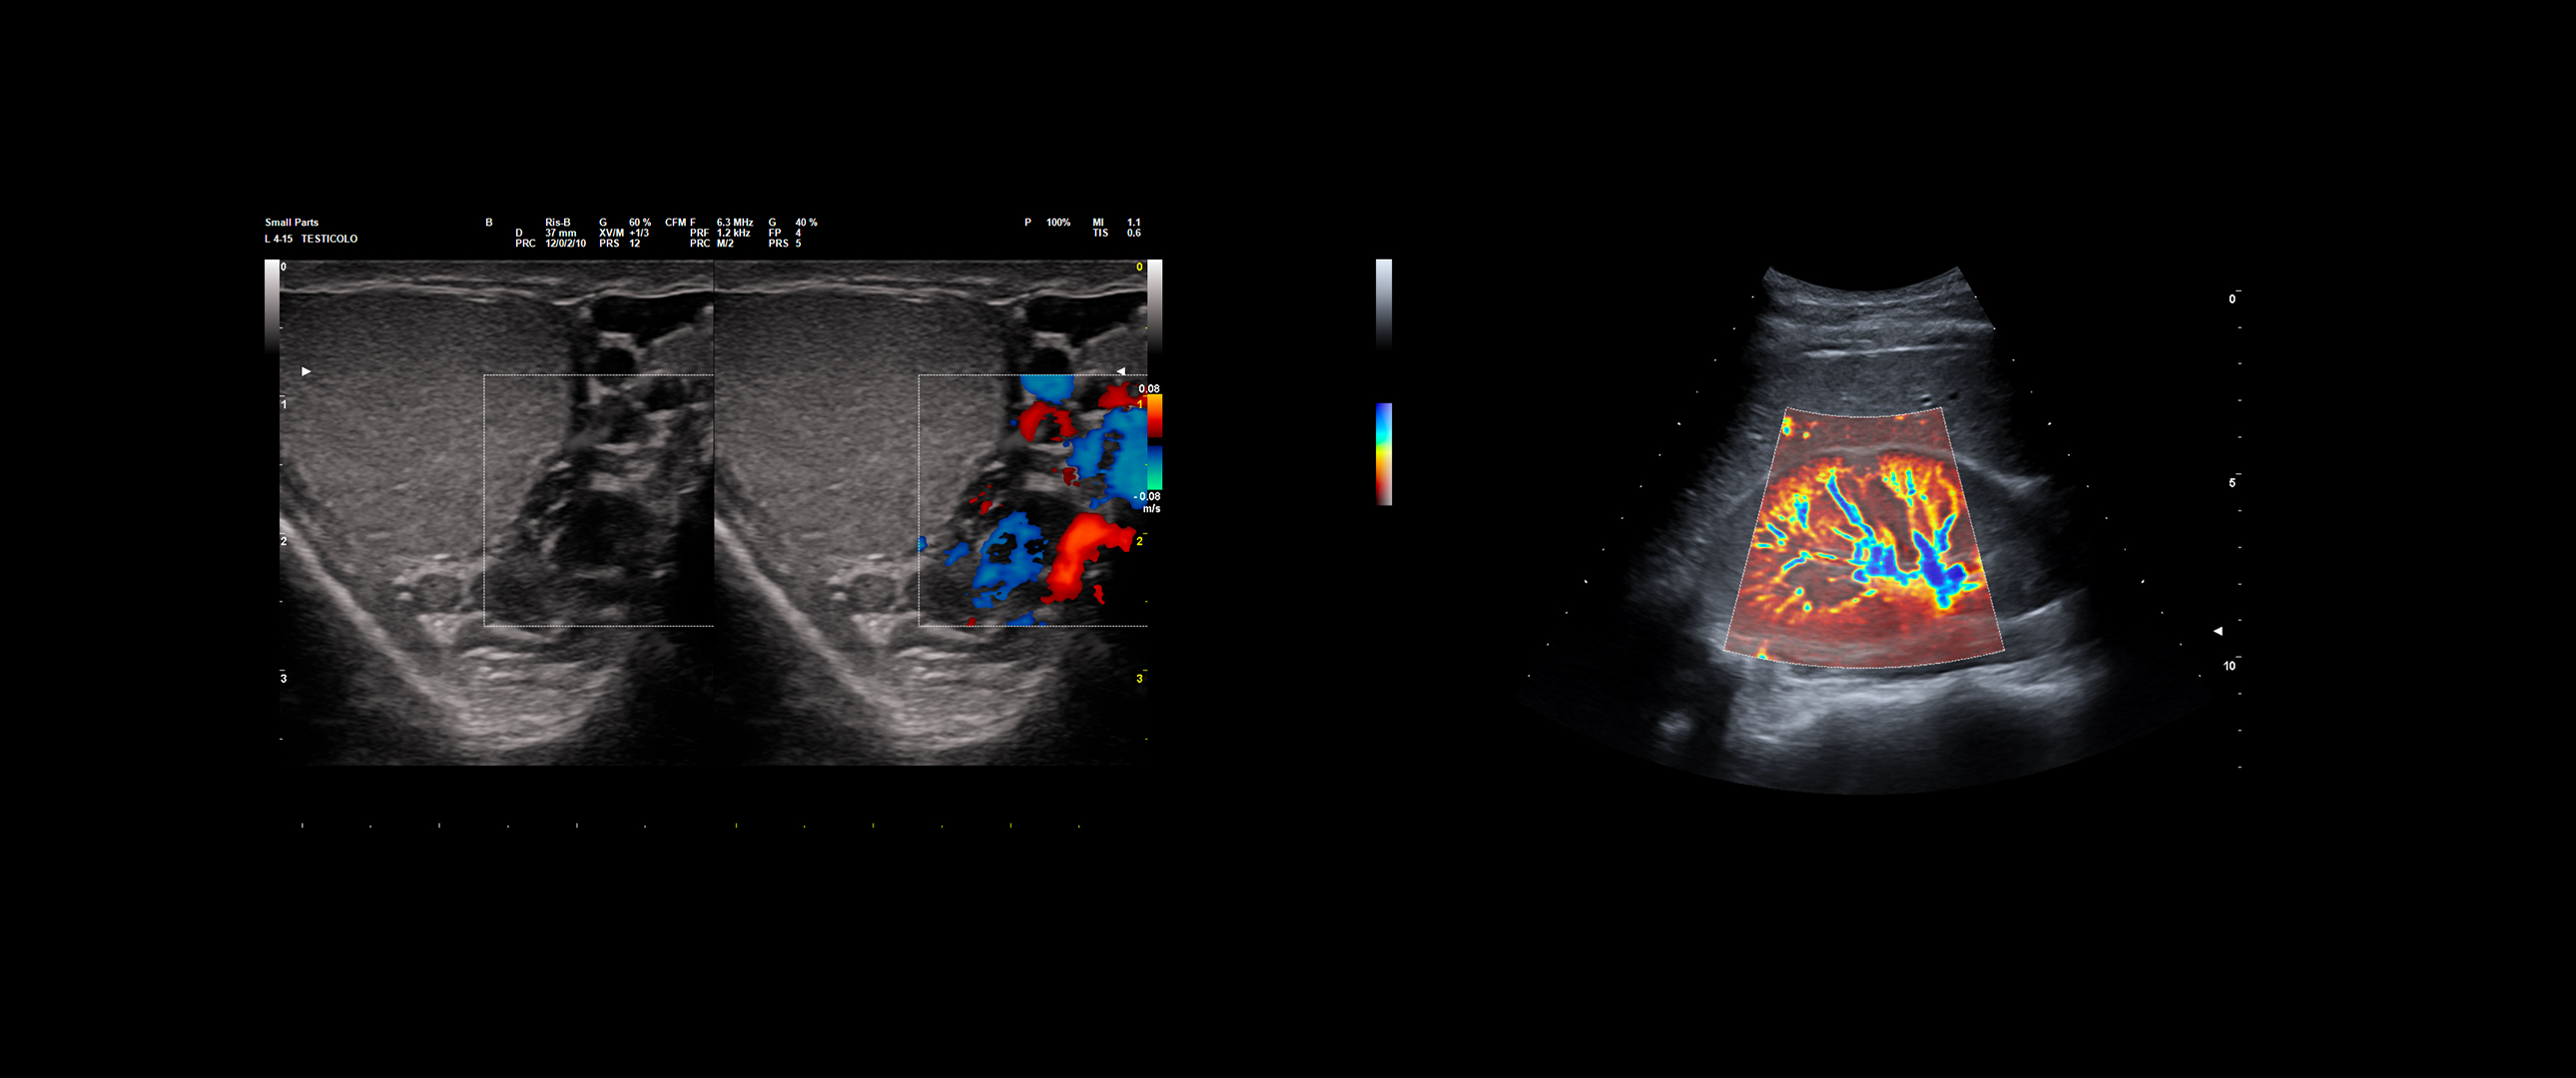

Thanks to a wide probe portfolio, Esaote extends and completes the use of ultrasound, from precise prostate assessment to accurate testicular and penile imaging, as well as advanced kidney and bladder examinations.

Together with the proprietary IQProbes technology, which provides high-quality B mode imaging, additional advanced imaging modes can be used to further enhance the user’s diagnostic confidence, especially in complex cases:

- microV

- QElaXto

- QElaXto 2D

- CnTI™

Testis Varicocele under HF linear transducer examination - Micro-vascularization on kidney through microV